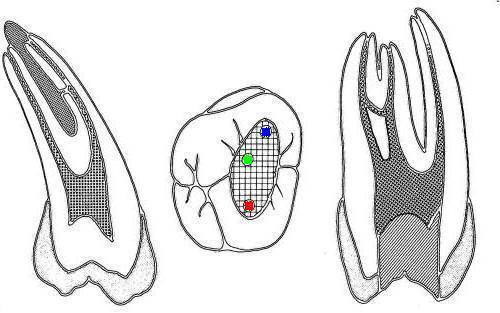

1º molar inferior (1,2,23,27)

En azul conducto mesio-vetibular

-

En verde conducto mesio-lingual

En rojo conducto distal

En amarillo un cuarto conducto,

si el conducto distal se encuentra desplazado hacia lingual,

existe una alta posibilidad de encontrar un cuarto conducto

|

Tres

conductos en piso de cámara pulpar, el conducto

distal se encuentra ensanchado en sentido

buco-lingual, debe sospechar la existencia de

dos conductos que comparten el orificio de entrada.

Cámara intraoral X10 aumentos. |